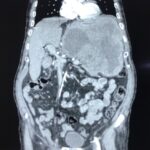

Վիրաբուժության կլինիկայի ղեկավար, պրոֆեսոր Սուրեն Ստեփանյանի կողմից իրականացվել է հերթական բարդ վիրահատությունը. հեռացվել է ստամոքսի հսկա ուռուցք, որը տարածված էր որովայնի վերին հարկում: Հիվանդի նախավիրահատական հետազոտություններից և նախապատրաստությունից հետո, վիրաբույժների թիմը (պրոֆ. Ս. Ստեփանյան, Հ.Սաֆարյան, Վ. Մանվելյան) իրականացրել է վիրահատություն ընդհանուր անզգայացման տակ (անեսթեզիոլոգ Ա. Ղազարյան): Վիրահատության ժամանակ ռևիզիայով պարզվել է, որ ստամոքսի ուռուցքը սերտ կպած էր փայծաղին, ընդգրկել էր ենթաստամոքսային գեղձի պոչի շրջանը և փայծաղի անոթները:

Ուռուցքի հեռացման համար կատարվել է ստամոքսի պատի ծավալուն մասնահատում, ենթաստամոքսային գեղձի դիստալ մասնահատում, փայծաղի հեռացում, խոլեցիստէկտոմիա: Նշված հյուսվածքները հեռացվել են մեկ բլոկով: Հեռացված մակրոպրեպարատի չափերն էին 35սմх25սմх15սմ: